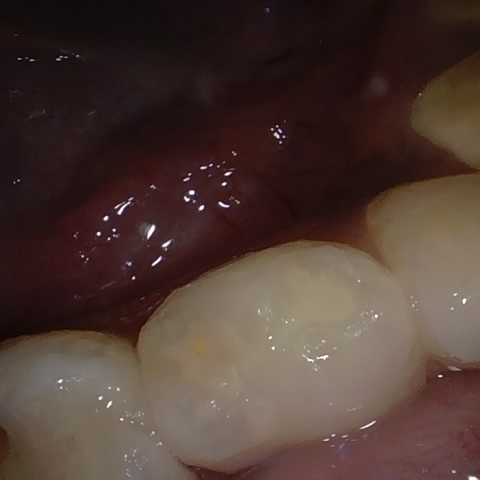

Annotated as "Good"